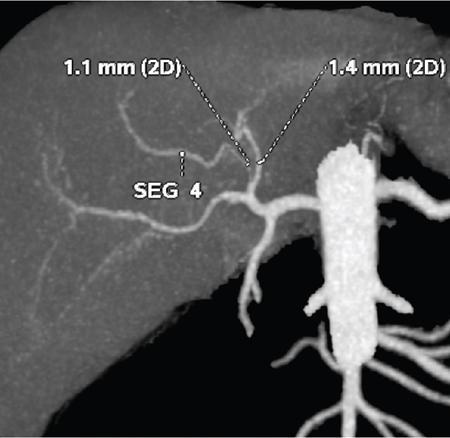

Ritu K. Kashikar, Shrinivas B. Desai Knowledge regarding normal dimensions of organs is important as visceromegaly is the first and often only abnormality in a variety of disorders. The radiologist should also be aware of normal diameters of vessels and ducts because an increase in size is usually a pointer to pathology in the organ. This chapter is a lucid review of normal sizes of organs, vessels, duct and also focuses on which section and location should size be measured to avoid interobserver variation. The liver is the largest organ in the abdomen. Hepatomegaly is a common condition and often the first clinical and imaging feature of various disorders. It is hence imperative for the radiologist to know the normal size and the section on which measurements should be taken. USG is commonly used to measure liver size. The longitudinal view is commonly used to measure liver size. The liver is considered normal in size if on longitudinal scan through the midhepatic line the liver measures 13 cm or less. This is true in approximately 93% individuals Measurement more than 15.5 cm suggests hepatomegaly in 75% cases (Figs. 9.3.1 and 9.3.2) (Table 9.3.1). Hepatomegaly is also suggested by an inferior angle of more than 45 degrees in the left lobe and more than 90 degrees in the right lobe. The normal liver measures approximately 6.5 cm first 3 months of age and reaches a size of 12.5 cm by 10–12 years of age. Liver size can be measured on unenhanced or enhanced CT. On CT the liver measures 10–12.5 cm in the midclavicular line on an average. A liver measuring more than 15.5–16 cm in the midclavicular line is considered enlarged. The midclavicular line measurement is done in coronal plane (Fig. 9.3.3). Another important measurement is the size of caudate lobe. The caudate to right lobe ratio (C/RL) is a measurement used to diagnose caudate lobe hypertrophy and right lobe atrophy which is important in the diagnosis of cirrhosis. The axial section immediately below main portal vein bifurcation is used for measurements. The following lines are drawn on the liver (Fig. 9.3.4). C/RL: In an adult patient of average weight (60 kg), the estimated liver volumes can range from 1024–1302 cm3 (Fig. 9.3.6). USG and Doppler provide important information regarding patency of artery in postoperative/transplant setting. Normal hepatic artery waveform is pulsatile and of low resistance. The normal resistive index measures 0.7. High or low resistivity index (RI) indicated pathology. The measurements of the hepatic arteries bare importance in transplant imaging. The diameter and length of the arteries are best measured on CT angiogram images. Arteries smaller in calibre than 2 mm may be difficult to anatomize. Replaced RHA is often longer in length than standard arteries. The normal diameters of the hepatic arteries are mentioned in Table 9.3.2 (Figs. 9.3.7–9.3.9). The portal venous system is valveless and hence its diameter is influenced by respiratory variations. The portal venous diameter is greatest during inspiration and hence all measurement should be made in this phase (Table 9.3.3). The diameter of portal vein has importance in diagnosing portal hypertension and USG is often used for this purpose. USG also provides other important parameters like flow velocity and volume flow which are relevant in the setting of portal hypertension. The normal portal venous velocity measures 15–18 cm/sec.(Fig. 9.3.10)

Hepatic artery

Common hepatic artery

0.50 ± 0.04 cm

Hepatic artery proper

0.45 ± 0.03 cm

Left hepatic artery

0.30 ± 0.03 cm

Right hepatic artery

0.36 ± 0.04 cm